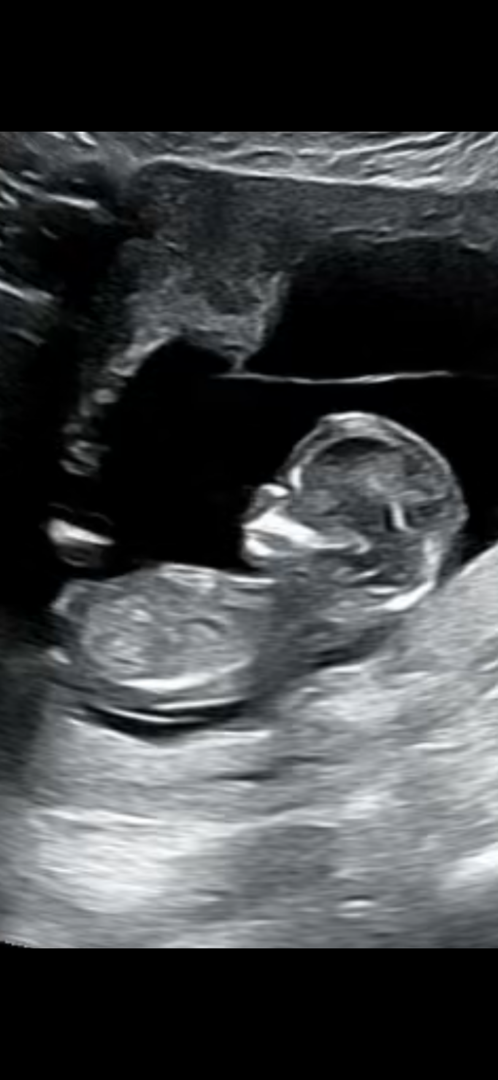

혹시 이 초음파사진으로도 각도법 알수있을까요~?

이제 곧 13주차되는 예비아빠 입니다~! 다른분들 올리신 각도법 사진을봐도 저는 잘 모르겠네요 ㅎㅎ 의사선생님도 초음파 보시곤 아직 애매하다고 하시더라구요ㅎㅎ 혹시 이 사진으로도 예상해볼수 있을까요~?